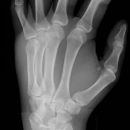

Hand a.p. (dorsovolar)

Lagerung

Patient sitzt seitlich am Tisch, der abgewinkelte Unterarm und die Handflächen liegen auf, Finger leicht gespreizt, evtl. Sandsack zur Fixierung auf den Unterarm legen.

Zentralstrahl

Auf Objekt- und Kassettenmitte.

Anmerkung

Übersichtsdarstellung des Skeletts bei Frakturen, Arthrosis und Deformierung der Gelenke, sowie chronischer Polyarthritis (Rheuma).

Qualitätskriterien

Vollständige Abbildung der ganzen Hand einschließlich aller Fingerendglieder und des Handgelenkes.